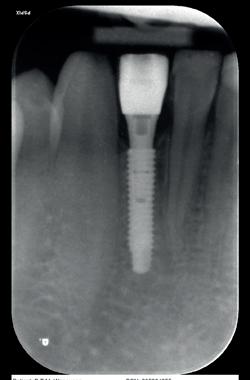

Hij heeft een CBCT-scan gemaakt en na extractie de 13 vervangen door een implantaat. Er was nog wat onduidelijkheid over de status van de 11, dus we hebben hem expliciet laten kijken naar het vermeende resorptiedefect. Dit bleek echter een groot foramen incisivum, dus een overprojectie, zelfs in de vorm van een hartje (afbeelding 19, met dank aan Irfan Abas).

Röntgenologisch waren er evenmin bijzonderheden waar te nemen, de implantaten zagen er stabiel uit (afbeelding 20 en 21, met dank aan Irfan Abas). De diagnose was dan ook gezonde pulpae 41, 31 en geen bijzonderheden voor de overige tanden.